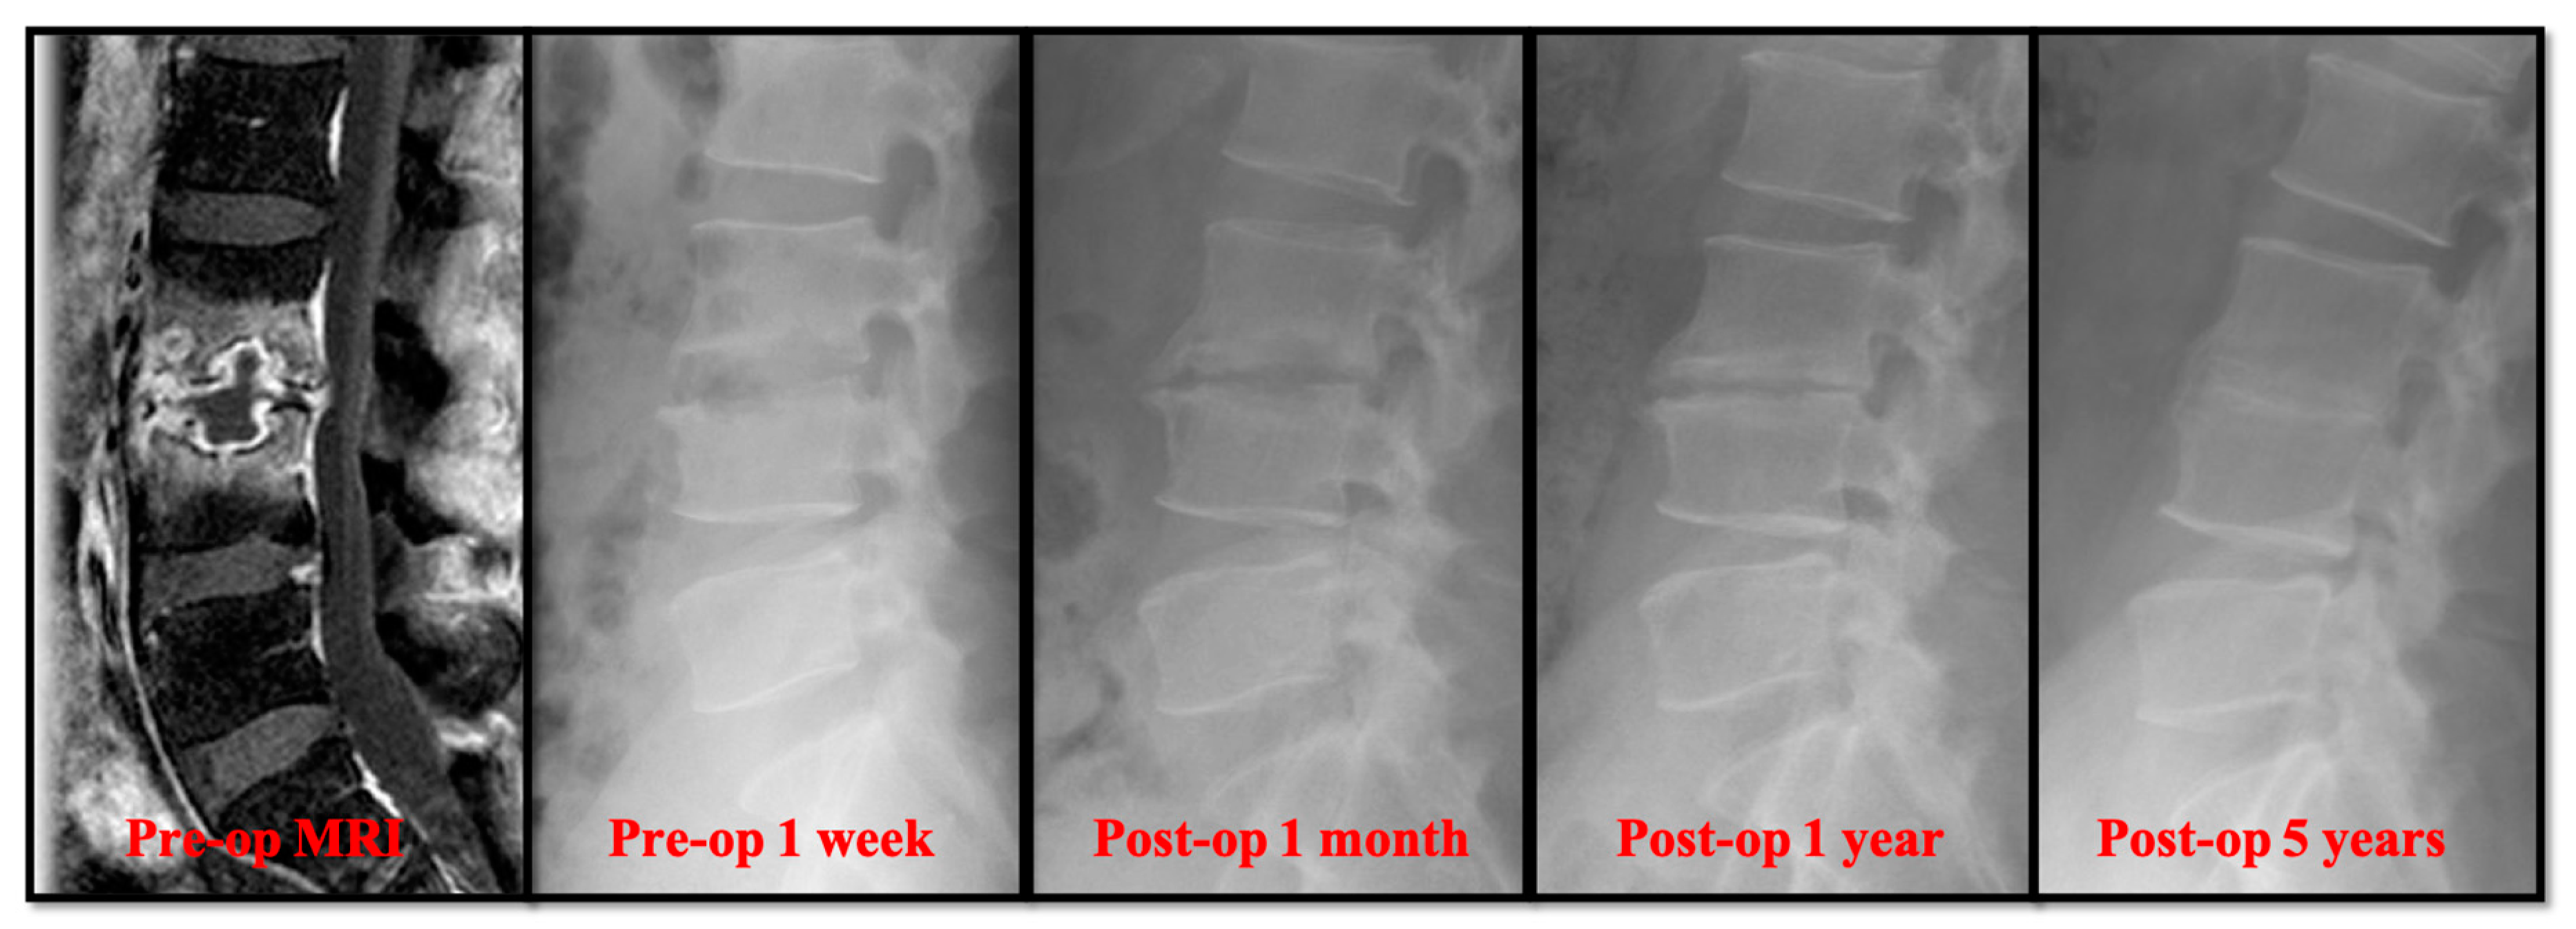

Radiographically, the primary correction gain after surgery was slightly higher in the open surgery group (Table 2). However, there was no significant difference in the change of sagittal profile, including primary correction gain (2.20° ± 2.91° versus 3.04° ± 3.65°), correction loss (2.41° ± 3.92° versus 3.68° ± 2.76°), and actual correction gain/loss (−0.21° ± 5.59° versus −0.64° ± 5.01°). In the follow-up radiographs, the successful bony fusions of the infected segments appeared in most of the anterior open surgery cases (Figure 1). A successful bone fusion was determined by continuously trabecular bony bridging between vertebrae and bone graft. There was no change in the sagittal angle of the targeted spinal segment between flexion-extension dynamic plain radiographic views because not every patient would consent to computerized tomography scans. Twenty-six out of 30 (86.7%) open surgery patients showed solid fusion at two years for the follow up. Nevertheless, 8 patients had obvious subsidence of the bone grafts due to damaged endplates in the early periods. Conversely, the destructive endplates of the infected segments became sclerotic, although decreased intervertebral disc height and local kyphosis were observed after successful treatment in the PEDD group (Figure 2). However, the motion of these infected spinal segments was still preserved after successful PEDD treatment. In the longer follow up, two patients showed spontaneous fusion in the PEDD group (Figure 2).

Figure 2. A 36-year-old man presented with severe pain in the lower back and leg. He was diagnosed with L3–L4 methicillin-resistant Staphylococcus aureus infection. The destructive endplate of the infected L3–L4 segment became sclerotic change although decreased intervertebral disc height and local kyphosis were observed after successful treatment in the PEDD group.